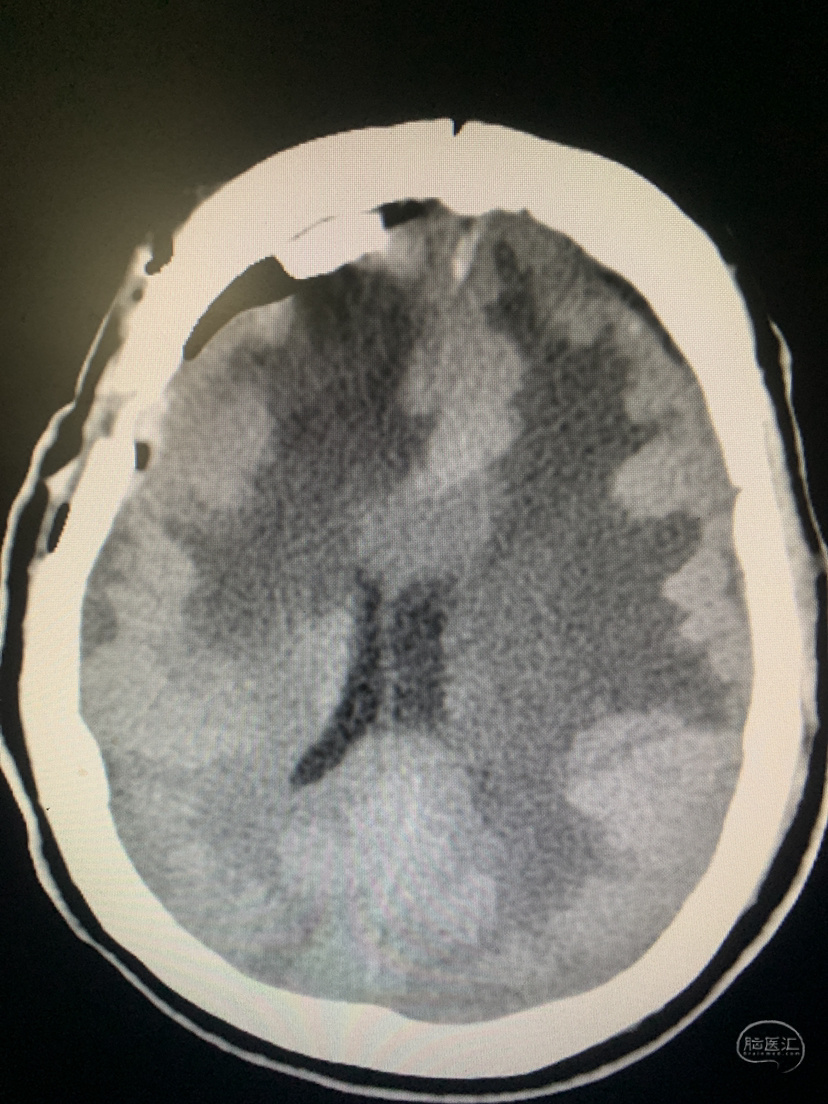

术前术后对比

术后CT